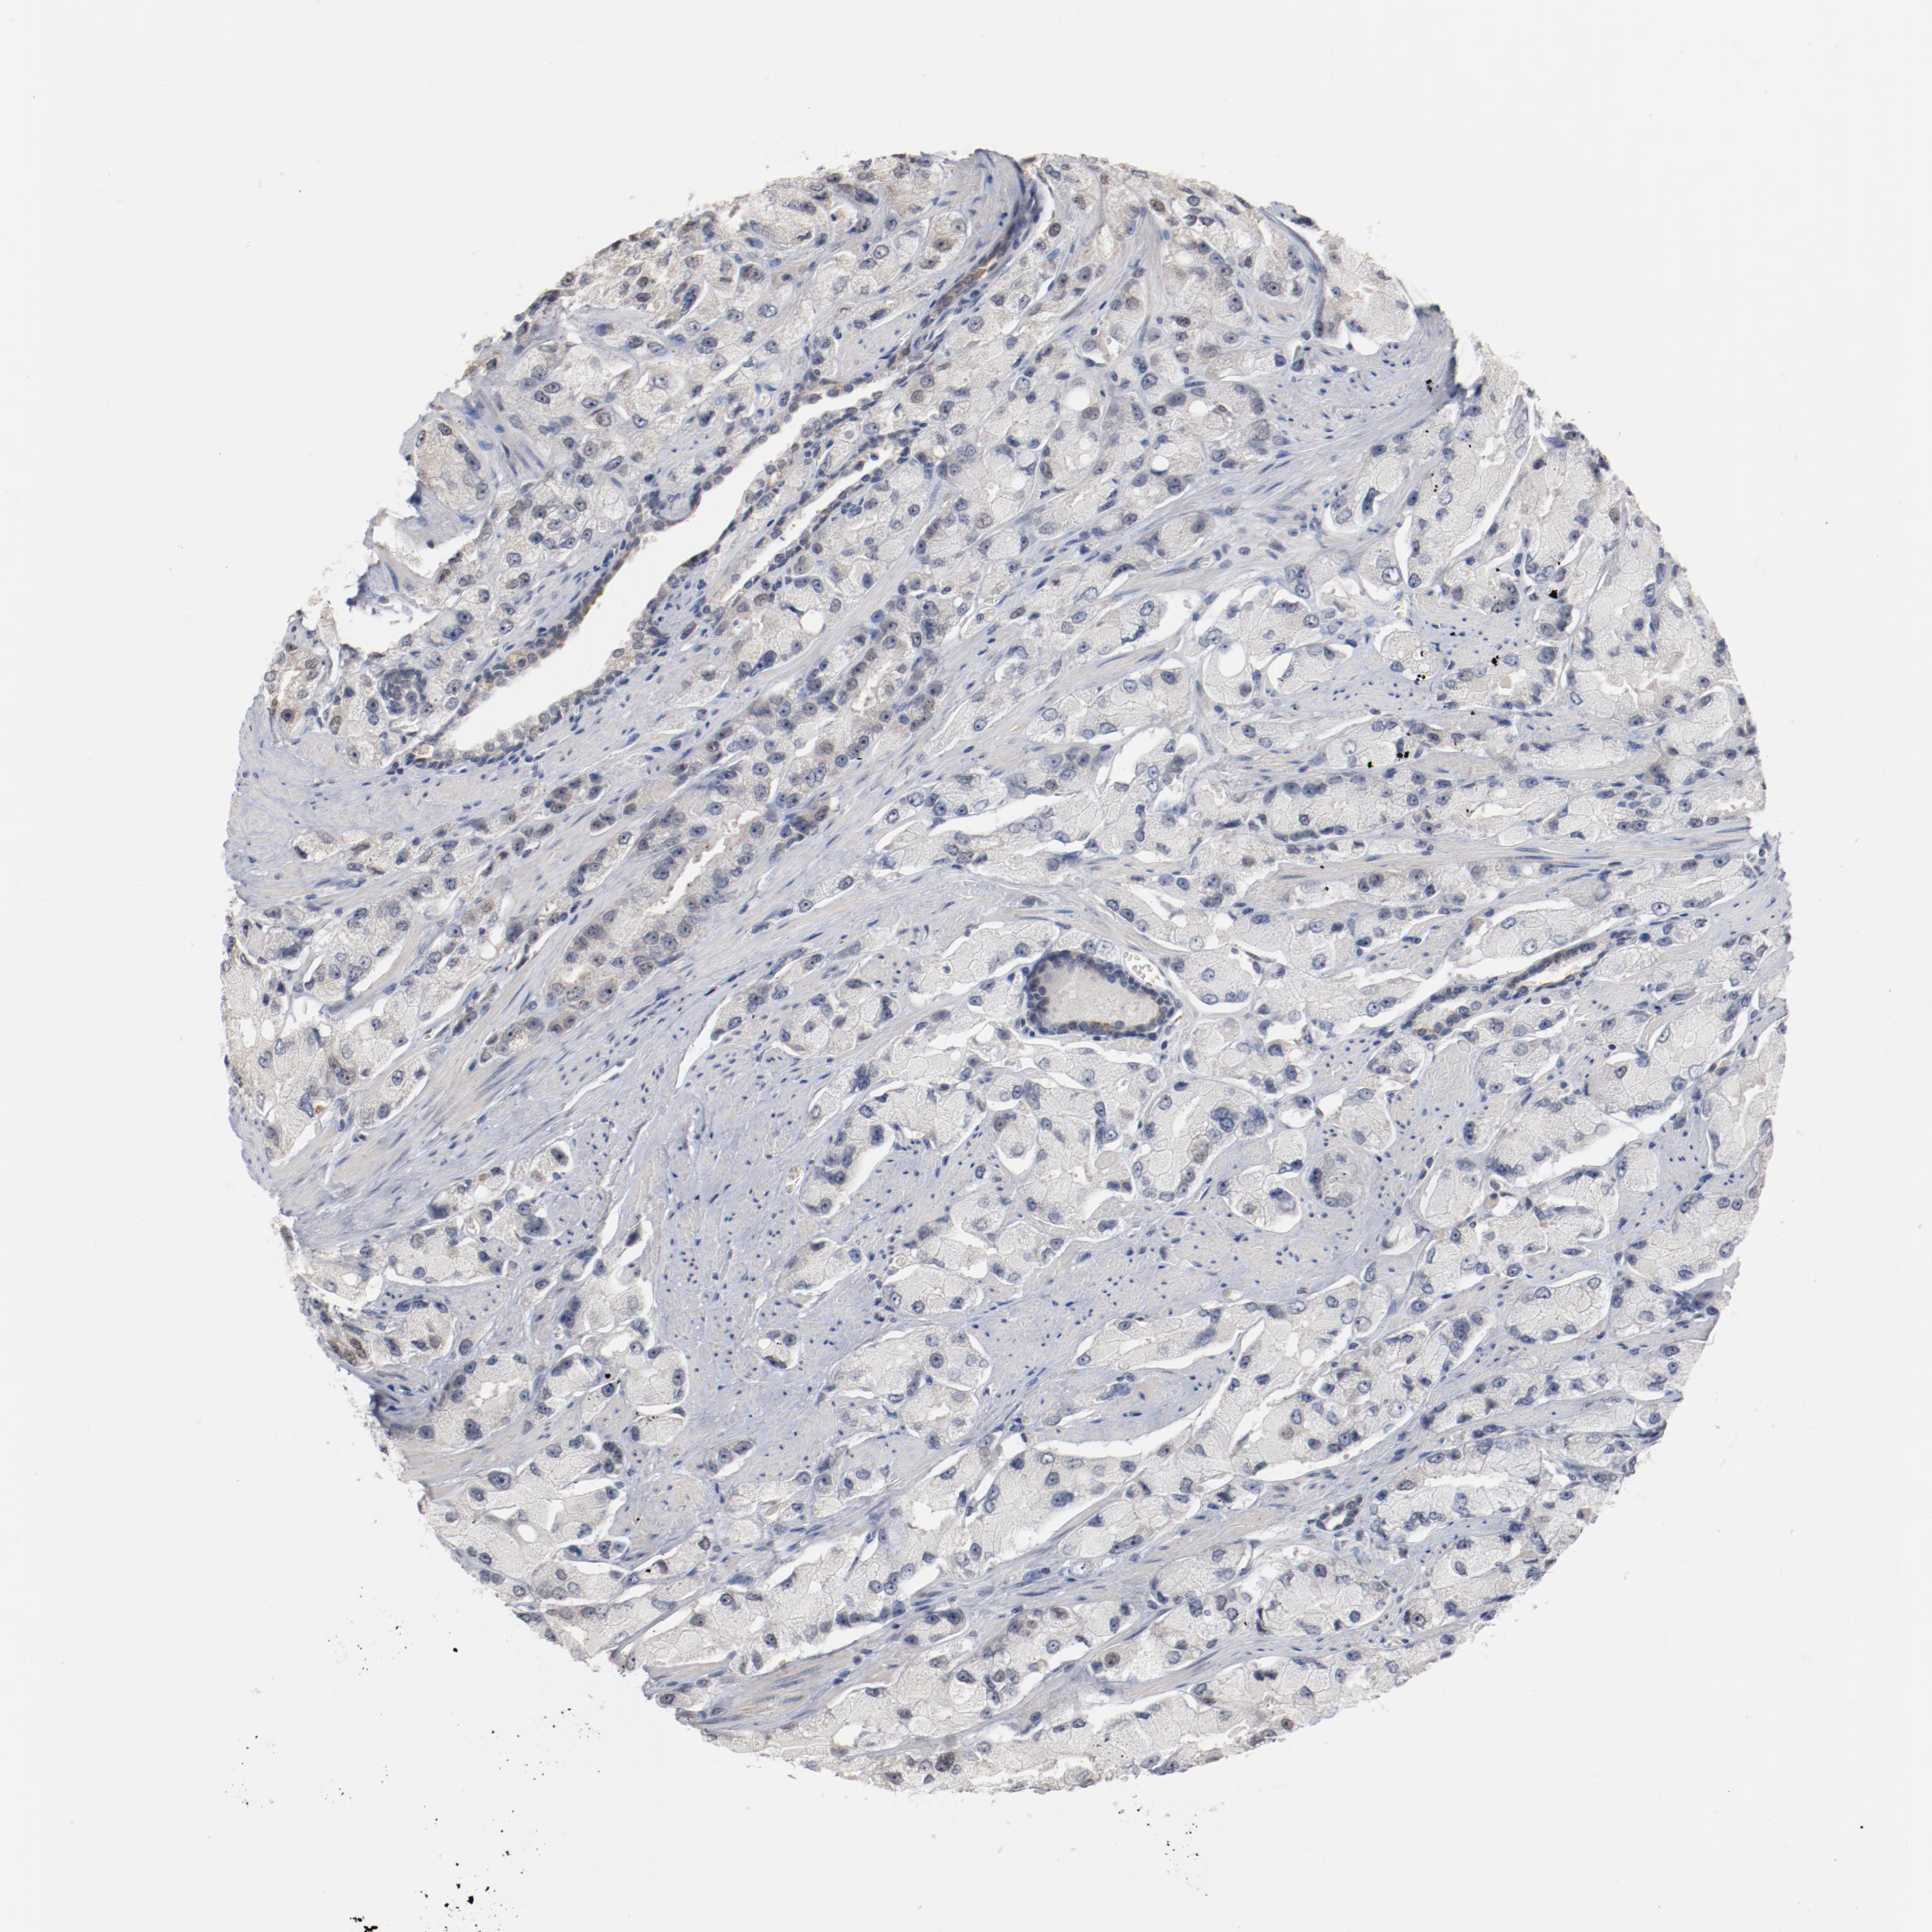

PROSTATE CANCER - Protein expressioni

A mouse-over function shows sample information and annotation data. Click on an image to view it in a full screen mode. Samples can be filtered based on level of antibody staining by selecting one or several of the following categories: high, medium, low and not detected. The assay and annotation is described here.

Note that samples used for immunohistochemistry by the Human Protein Atlas do not correspond to samples in the TCGA dataset.

Antibody stainingi

Antibody staining in the annotated cell types in the current human tissue is reported as not detected, low, medium, or high, based on conventional immunohistochemistry profiling in selected tissues. This score is based on the combination of the staining intensity and fraction of stained cells.

Each image is clickable and will lead to virtual microscopy that enables deeper exploration of all samples and also displays staining intensity scores, fraction scores and subcellular localization as well as patient and tissue information for each sample.

Antibody HPA003725

Staining

High

Medium

Low

Not detected

Intensity

Strong

Moderate

Weak

Negative

Quantity

>75%

75%-25%

<25%

None

Location

Nuclear

Cytoplasmic/membranous

Cytoplasmic/membranous,nuclear

Adenocarcinoma, Low grade

Adenocarcinoma, Medium grade

Adenocarcinoma, High grade